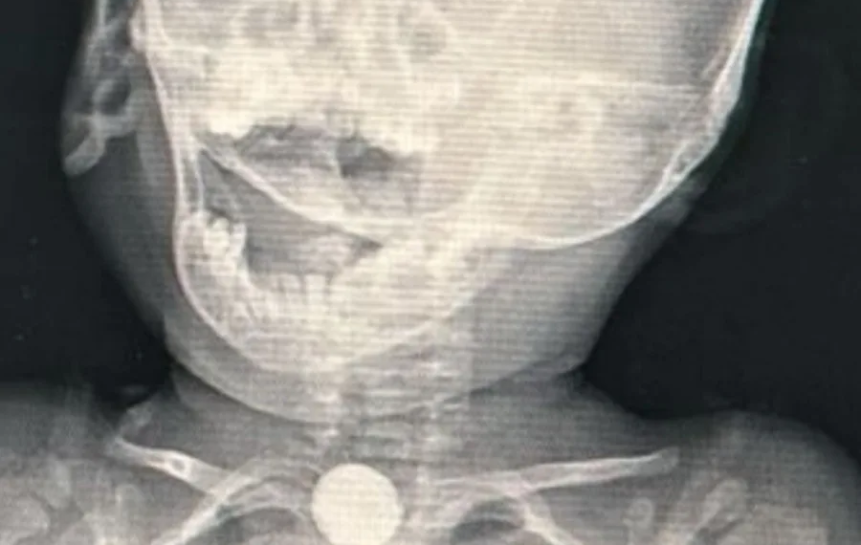

Uma bebê indígena de apenas um ano, da etnia Ashaninka, precisou ser levada de Marechal Thaumaturgo a Cruzeiro do Sul após engolir uma bateria de brinquedo. O caso ocorreu dois dias antes de sua chegada ao hospital, e o cirurgião geral Marlon Holanda, que atua na cidade, realizou o procedimento de remoção e fez um alerta aos pais sobre os riscos.

Segundo o médico, a mãe da criança inicialmente hesitou em buscar atendimento, por não falar português com fluência, mas foi convencida a procurar ajuda. Uma radiografia identificou que o objeto ingerido era uma bateria, que deve ser retirada em até duas horas após a ingestão para evitar sérias complicações.

“A bateria é extremamente perigosa, porque pode se romper e liberar elementos químicos que causam graves lesões internas. Nós a removemos no domingo pela manhã. Havia lesões severas na mucosa do esôfago, mas, felizmente, ainda não houve perfuração”, explicou o médico.